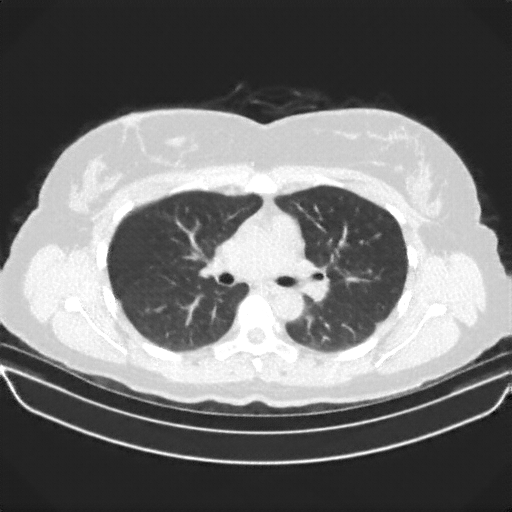

Targeted Slice 70 - HU-Space Analysis (Generated vs Real Venous)

0.885

HU SSIM

91.7

HU RMSE

40.0

HU MAE

Average HU-Space Metrics Across All Slices (170 slices) - Generated vs Real Venous

0.886

HU SSIM (Avg)

96.8

HU RMSE (Avg)

41.0

HU MAE (Avg)

Image Grid

4Γ—3 grid: Rows show different image types (Original NATIVE, Reconstructed NATIVE, Original VENOUS, Generated VENOUS), Columns show windowing techniques (No Window, Lung Window, Mediastinum Window)

Original VENOUS CT scan

Lung window (WL -600, WW 1500 β†’ Low βˆ’1350, High +150)